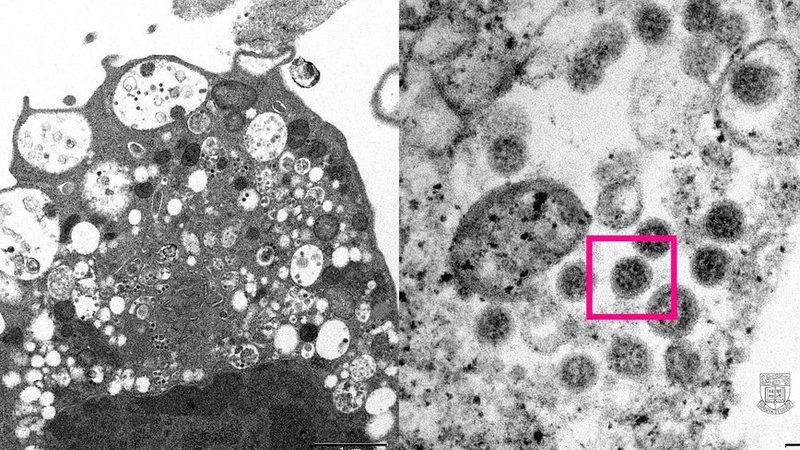

Dois cientistas da Universidade de Hong Kong divulgaram, na quarta-feira (8), as duas primeiras imagens da variante Ômicron do coronavírus. Segundo informações da instituição, as imagens foram capturadas por meio de microscópio. A nova cepa foi identificada pela primeira vez na África do Sul.

Conforme a primeira imagem, é possível identificar a célula de um rim de macaco após infecção com a variante. Há danos celulares com veículas inchadas e contém pequenas partículas de cor preta.

Na imagem à direita, a célula está infectada. Na parte que tem uma caixa vermelha, há partículas virais com pontas em forma de coroa.